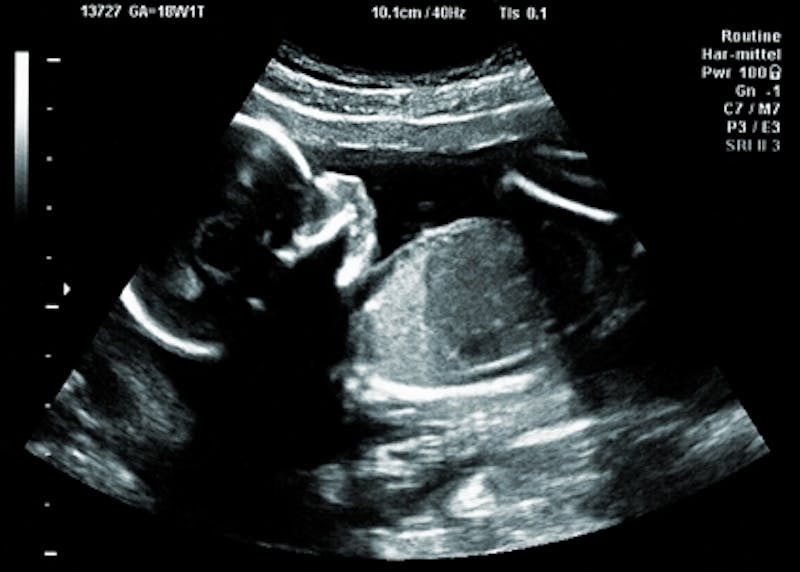

Understanding Article 119a (Death or Injury of an Unborn Child)

Few things are more tragic and gut-wrenching than the death or injury of an unborn child. Under Article 119a of the Uniform Code of Military Justice (UCMJ), a service member who commits a violent crime that results in the death or injury to an unborn child may be prosecuted not o...